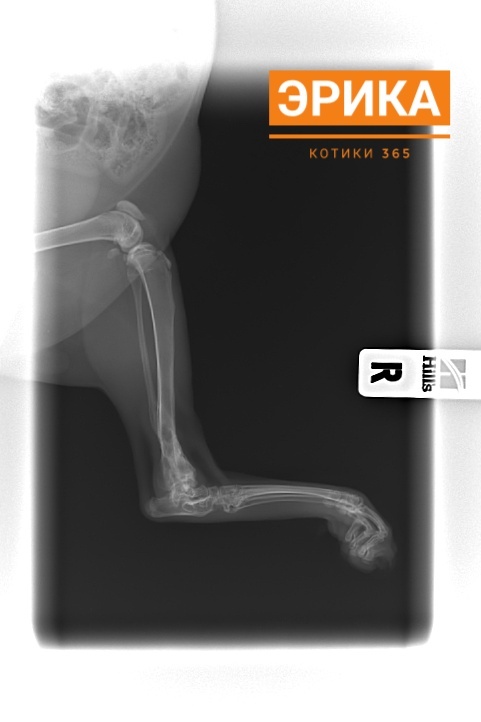

Сегодня Эрика была в клинике на снятии швов и сделала рентген.

По рентгену все срослось хорошо.

"У скакательного сустава восстановлена полная амплитуда движений без ограничений ".

Результат превзошёл ожидания и прогнозы.

Эрика теперь может прыгать и бегать, как будто никакого перелома и не было.